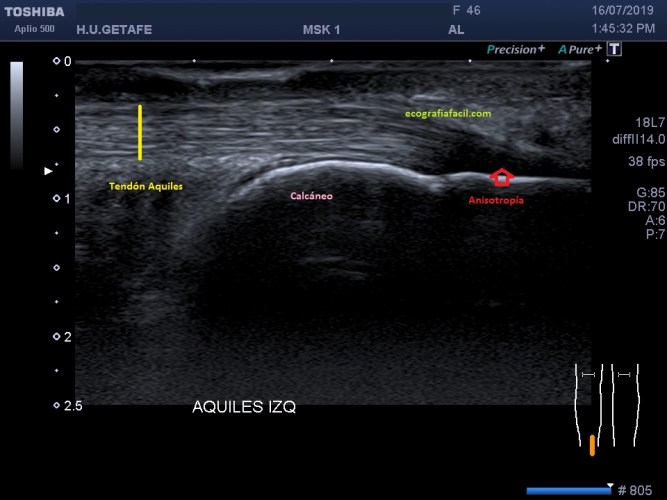

En la imagen número 1 podemos ver una imagen bastante habitual en el estudio del aquiles, marcado con flecha roja, vemos una zona de hipoecogenicidad que corresponde al cambio de angulación de las fibras que en la zona de inserción se objetivan claramente hipoecogénicas en relación con anisotropía.